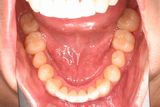

成人の叢生2(唇側矯正装置、非抜歯)

初診時口腔内写真

歯の凸凹を気にされての来院です。上顎右側の小臼歯が一本欠如していました(先天的欠如なのか抜歯したのかは問診からは判断できませんでした)。上顎の凸凹よりも下顎の凸凹の方が酷く、かつ上顎の歯が一本少ないので、下顎の右側大臼歯の後方移動+下顎切歯を僅かに削合することにより叢生改善のためのスペースを獲得することにしました。